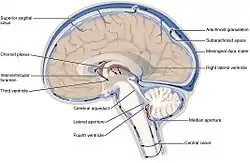

The cerebrospinal fluid circulates in the subarachnoid space around the brain and spinal cord, and in the ventricles of the brain. | |

Image showing the location of CSF highlighting the brain's ventricular system | |

CSF occupies the subarachnoid space (between the arachnoid mater and the pia mater) and the ventricular system around and inside the brain and spinal cord. It fills the ventricles of the brain, cisterns, and sulci, as well as the central canal of the spinal cord. There is also a connection from the subarachnoid space to the bony labyrinth of the inner ear via the perilymphatic duct where the perilymph is continuous with the cerebrospinal fluid. The ependymal cells of the choroid plexus have multiple motile cilia on their apical surfaces that beat to move the CSF through the ventricles.

There is about 125–150 mL of CSF at any one time.[1] This CSF circulates within the ventricular system of the brain. The ventricles are a series of cavities filled with CSF. The majority of CSF is produced from within the two lateral ventricles. From here, CSF passes through the interventricular foramina to the third ventricle, then the cerebral aqueduct to the fourth ventricle. From the fourth ventricle, the fluid passes into the subarachnoid space through four openings – the central canal of the spinal cord, the median aperture, and the two lateral apertures.[1] CSF is present within the subarachnoid space, which covers the brain and spinal cord, and stretches below the end of the spinal cord to the sacrum.[1][2] There is a connection from the subarachnoid space to the bony labyrinth of the inner ear making the cerebrospinal fluid continuous with the perilymph in 93% of people.[3]